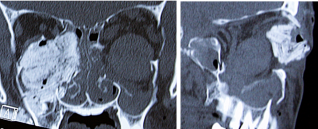

In typical globe luxation, the globe is visualized outside the orbit but in rare situations, the patient may present with an ‘empty socket’. In such situations, the globe may be prolapsed into one of the paranasal sinuses (maxillary sinus followed by the ethmoid sinus).[1][35][27][41] Displacement of the globe into paranasal sinus can be easily explained by large displaced blow out fractures. Careful examination should be performed when the trauma involves the ethmoid sinus due to the proximity of the skull base with potential CSF leak (‘liquor fistula’).[42] Even more rarely, globe luxation into the into the anterior cranial fossa may occur following by extensive and displaced frontal fracture of orbital roof, with a combination of high intraorbital pressure and dehiscence of the orbital roof as causative factors.[7][43][44]

A third mechanism is direct result of sudden reduction of the orbital cavity volume such as following large blow-in fractures, typically of the orbital roof.[3][32] Paradoxically, large displaced orbital wall blow out fractures may precipitate a globe prolapse into one of the paranasal sinuses – most commonly the maxillary sinus and less commonly the ethmoidal sinus and even more rarely the intracranial cavity.[3][25][33][34][35]